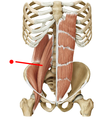

What are the muscles of the posterior wall of the abdomen?

- Psoas major

- Quadratus lumborum

Psoas Major

COURSE:

- Th. 12, L 1-4 side, L 1-5 cost. proc. > lesser trochanter

ACTION:

- flex and ext. rotate hip

INNERVATION:

- lumbar plexus

Quadratus Lumborum

COURSE:

- internal lip iliac crest & iliolumbal ligament > rib 12, L 1-4 costal processes

ACTION:

- expiration

- flexes spine

INNERVATION:

- lumbar plexus